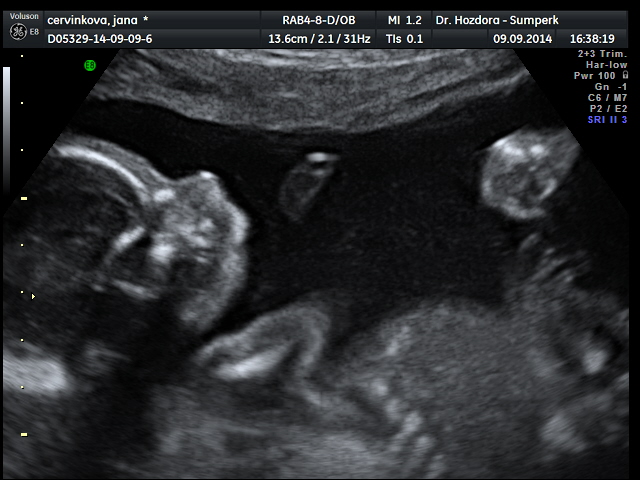

Děvčata,po dnešním ultrazvuku zvyšuju skore holčiček na 13:12. Bude to Marie Jana

Jsem tak happy.